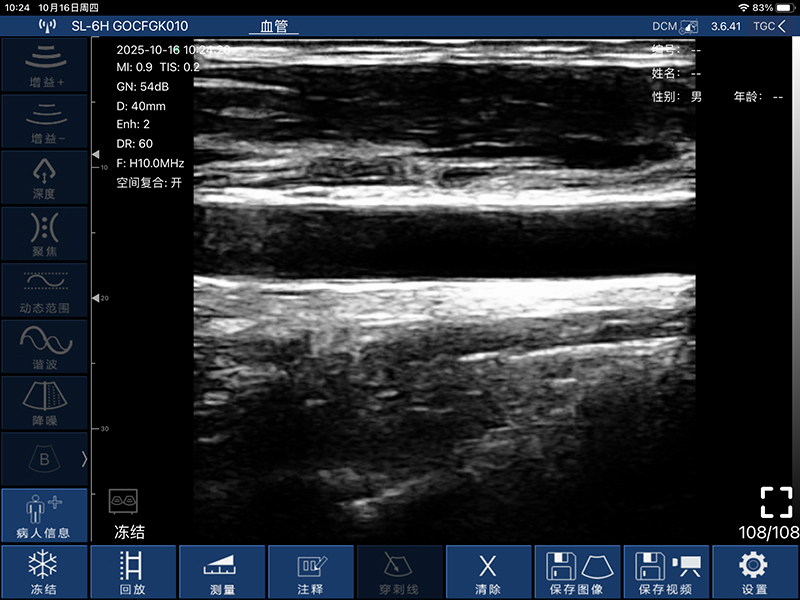

• 扫描方式:电子阵列扫描

• 探头频率:7.5/10MHz

• 扫描深度:20-100mm,可调

• 显示模式:B、B/M、Color、PW、PDI